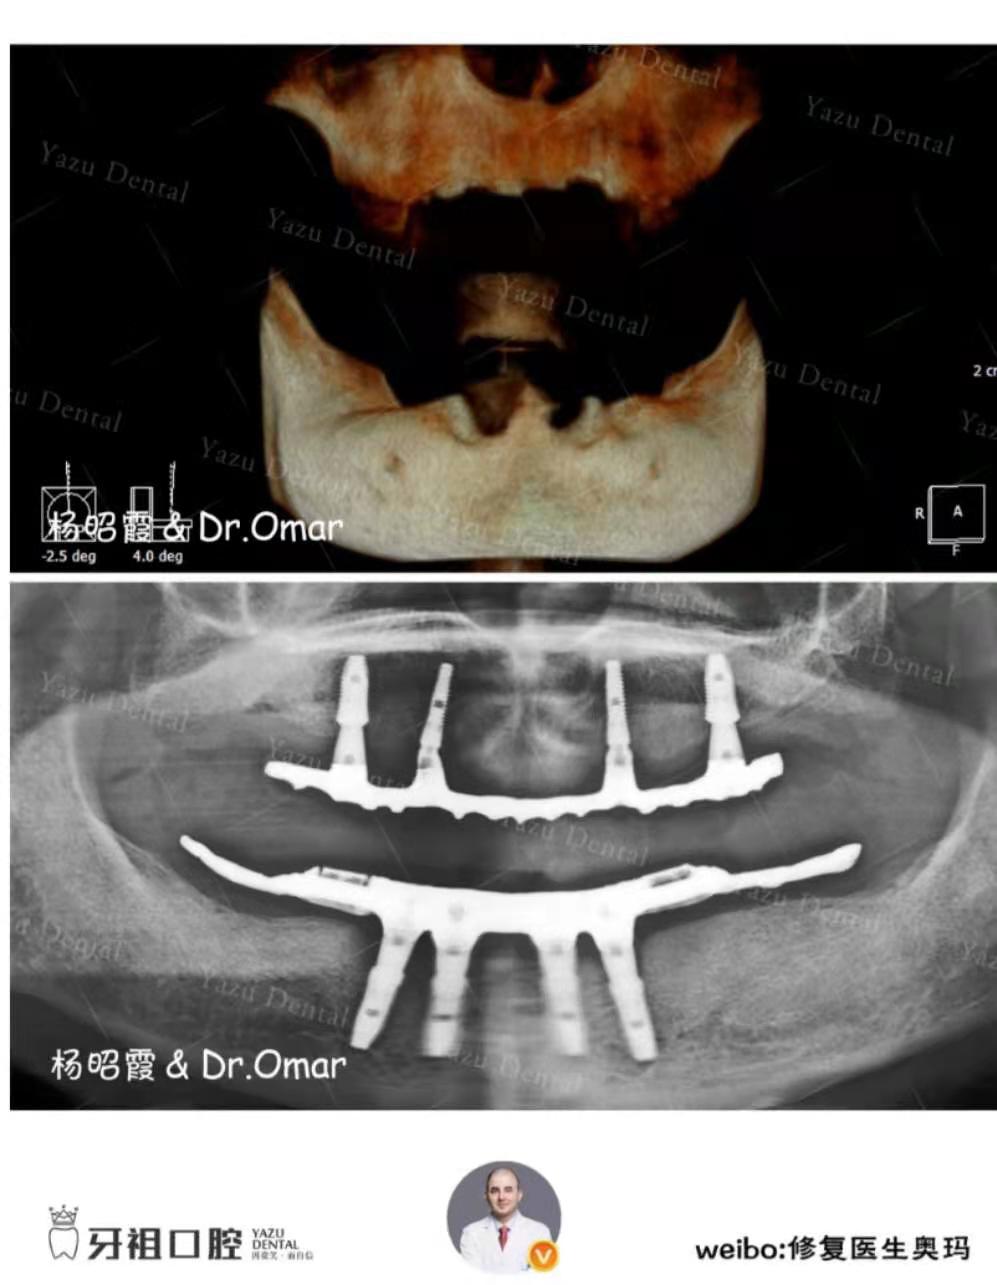

我们约的牙祖口腔的奥玛医生给我父亲看牙,医生给我父亲做检查,发现他的牙全口缺失了,下颌牙龈红肿。也是蛮严重的了,为了以后可以很好的吃饭,必须要进行种植了。还记得当时奥玛医生给我们的种植方案是:可做全固定种植或者半固定种植或活动牙。

种植结束之后父亲反馈说有牙之后方便多了,他半固定种植牙比之前舒适多了,据说它使用人工牙根,比较稳定,使用寿命长。更适合美学修复。

奥玛医生说半固定式的是需要三餐后取下来清洁的,不像全固定种植的就像自己的牙齿一样,只需要饭后刷牙进行清洁就好。但也还好。虽然没有固定种植那么方便,但是从实用性上来说父亲觉得也足够了。